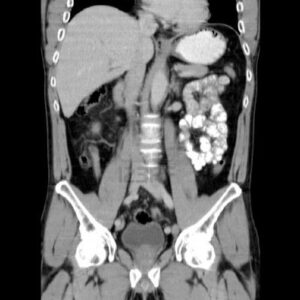

Le persone con una quantita' eccessiva di grasso addominale sono a maggior rischio per malattie cardiache e cancro rispetto a...

La Tac addominale che spesso si fa per altri motivi puo' essere utilizzata anche per diagnosticare l'osteoporosi senza bisogno dei...